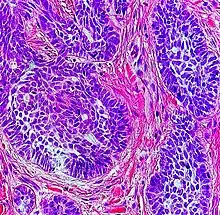

| Squamous-cell carcinoma of the skin | Squamous-cell carcinoma of the skin is generally distinguishable by for example relatively more cytoplasm, horn cyst formation and absence of palisading and cleft formations. Yet, a high prevalence means a relatively high incidence of borderline cases, such as basal-cell carcinoma with squamous cell metaplasia (H&E stain at left in image). BerEP4 staining helps in such cases, staining only basal-cell carcinoma cells (right in image). |  |